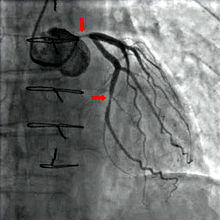

Angiography (left) and CT (middle and right) of chronic total occlusion lesions at the left anterior descending coronary artery (LAD) and right coronary artery (RCA).

CT angiography can act as a less invasive alternative to Catheter angiography. Instead of a catheter being inserted into a vein or artery, CT angiography involves only the injection of a CT-visible dye into the arm or hand via an IV line. CT angiography lowers the risk of arterial perforation and catheter site infection. It provides 3D images that can be studied on computer, and also allows measurement of heart ventricle size. Infarct area and arterial calcium can also be observed (however those require a somewhat higher radiation exposure). That said, one advantage retained by Catheter angiography is the ability of the physician to perform procedure such as balloon angioplasty or insertion of a stent to improve blood flow to the artery.[7]